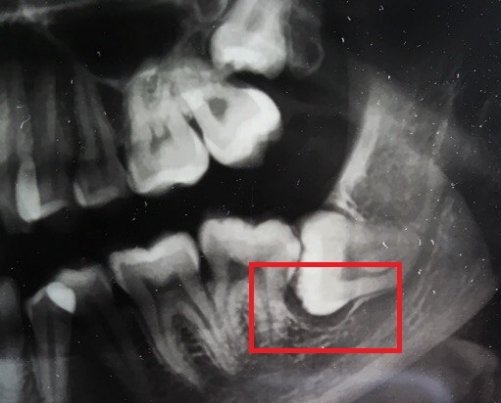

В подростковом возрасте мне сделали резекцию передних зубов из-за кисты. Но спустя примерно 15 лет над зубом образовался, на ощупь, шарик и очень неприятное напряжение под зубом. Я пошла к врачу, он отправил на снимок, но так и не смог мне помочь, и отправил к другому стоматологу, но попасть к нему я так и не смогла.

У вас так называемый рецидив. Обратитесь к хирургу, думаю, данный зуб придется удалить.